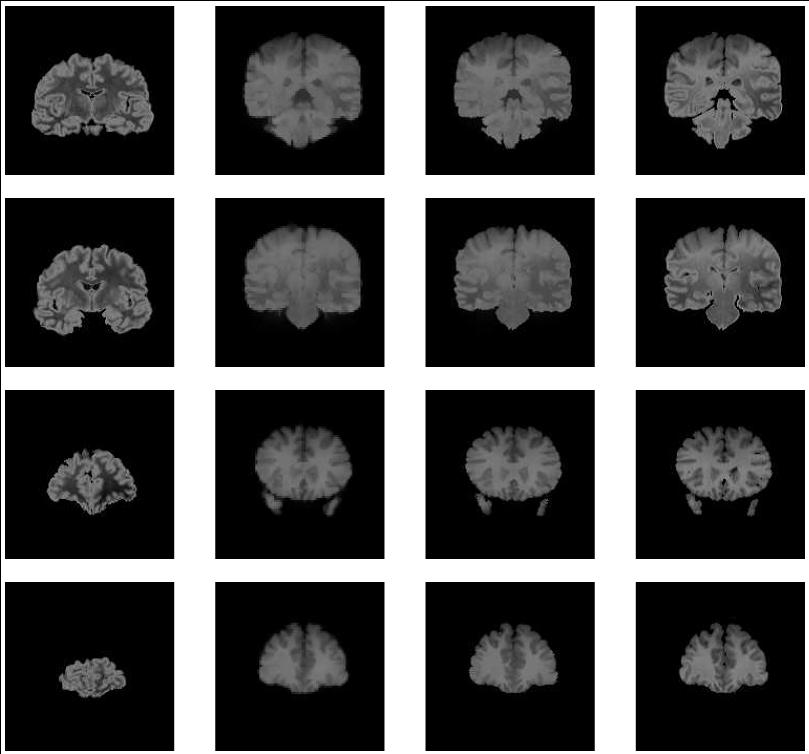

| our model | ![]() | ![]() | ![]() |

| fluid model | ![]() | ![]() | ![]() |

| deformed template | difference image before registration | edge map |

| slice 36 |

| |||

| slice 39 | ||||

| slice 54 | ||||

| slice 60 | ||||